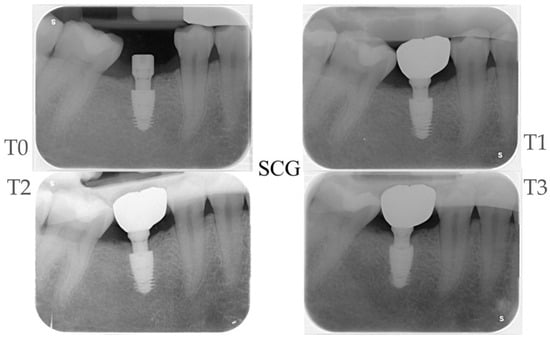

2.4. Radiographic Evaluations

| Time Points | MBM Control Group Δ (CI 95%) ** | p-Value | Bone Loss Control Group Δ (CI 95%) ** | MBM Test Group Δ (CI 95%) * | p-Value | Bone Loss Test Group Δ (CI 95%) ** | MBM Test vs. Control Δ (CI 95%) | p-Value |

|---|---|---|---|---|---|---|---|---|

| T1–T0 | −0.44 (−0.67; −0.21) | <0.01 | −0.44 (−0.67; −0.21) | −0.65 (−0.89; −0.42) | <0.01 | 0 | −0.21 (−0.54; 0.11) | 0.195 |

| T2–T0 | −0.49 (−0.72; −0.26) | <0.01 | −0.49 (−0.72; −0.26) | −0.72 (−0.95; −0.49) | <0.01 | 0 | −0.23 (−0.55; 0.10) | 0.168 |

| T3–T0 | −0.52 (−0.75; −0.29) | <0.01 | −0.52 (−0.75; −0.29) | −0.60 (−0.83; −0.36) | <0.01 | 0 | −0.07 (−0.40; 0.25) | 0.657 |